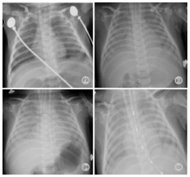

X线胸片提示双肺弥散渗出性病变,见图1。胸部螺旋CT平扫+增强提示双肺对称性斑片状毛玻璃样模糊影,见图2。

注:A、B、C为不同冠位

入院后予低流量吸氧,经皮氧饱和度(SpaO2)维持在93%~96%,先后经验性使用哌拉西林-他唑巴坦、口服阿奇霉素、头孢吡肟+万古霉素抗感染,静脉滴注氨溴索及布地奈德、可必特雾化等治疗。入院第4天纤维支气管镜检查提示呼吸道黏膜炎症。X线胸片示双肺弥散渗出性病变加重,见图1。入院第10天气促、呼吸困难加重,出现明显呼吸窘迫症状,SpaO2波动在87%~90%,咳嗽时伴口唇发绀,肺部听诊细湿啰音增多,复查床边胸片提示双肺弥散渗出进行性加重,见图1。改用气管插管机械通气,初始参数设置:吸入氧体积分数(FiO2)80%,呼吸道峰压(PIP)2.5 kPa,呼气末正压通气(PEEP)0.6 kPa,压力支持1.5 kPa, SpaO2维持在90%~95%。入院第10天在CT引导下经皮肺穿刺活检术,手术顺利。病理诊断:(肺)间质性炎症病变,见图3。应用甲泼尼龙2 mg/(kg·d)静脉滴注,1次/d,用药3 d后呼吸困难明显缓解,逐渐下调呼吸机FiO2、PIP、PEEP,复查胸片提示肺部渗出逐渐吸收好转,见图3。然后拔除气管插管改为鼻罩呼吸机辅助呼吸,3 d后脱离呼吸机改为鼻导管低流量吸氧,撤机后激素改为甲泼尼龙1 mg/(kg·d),静脉滴注,1次/d,3 d后改为泼尼松1 mg/(kg·d)口服,2次/d,7 d后停吸氧,激素总疗程14 d,住院25 d出院。出院时偶有干咳,无呼吸困难,一般情况好,出院后未继续口服激素。出院3个月门诊随访,患儿病情稳定,偶有咳嗽,无气促、呼吸困难,复查胸片示肺部阴影基本吸收;出院5个月电话随访一般情况好,无明显呼吸道症状,体质量增长良好。